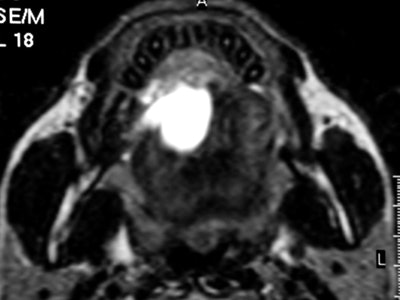

CT and MR are currently the primary imaging modalities to assess the oral cavity. CT is preferred in patients presenting with infectious/inflammatory syndrome. According to Borges, in patients presenting with oral cavity cancer, the use of dental CT software with the acquisition of para-axial and parasagittal high-resolution images in bone algorithm is most valuable in depicting early cortical bone erosion. MRI provides better soft-tissue resolution, and is the first choice in evaluating the deep extent of tumors and for the management of patients presenting with submucosal lesions.

Referring to the choice of imaging technique, she highlights the importance of considering different patients' specificities. Heavy smokers and drinkers prone to salivary stasis, difficulty in swallowing, and dyspnea are not good candidates for MRI, as this technique is very prone to motion artifacts, and patients with many dental fillings and/or dental implants may do better with MRI than with CT, she explained.

In terms of technical issues to note when imaging the oral cavity, Borges has plenty of good advice. She points out that dental-related artifacts can be avoided by angling the axial sections parallel to the dental fillings on CT or opting for MRI. When lesions are located in the gingival sulcus, jugal or palatal mucosa, or the tongue, cheek puffing is very helpful to clearly depict the full extent of the lesion and separate the lesion from the adjacent mucosal surfaces, she noted.

Whenever imaging a malignancy, the full extent of the neck should be imaged for nodal staging. Bone windows are required for all cases of cancer staging and whenever dentomaxillary pathology is suspected.

Finally, she emphasized that when using MRI, it is crucial to instruct a patient not to swallow and to breathe quietly during the entire examination. The use of surface coils can be very helpful for the imaging of superficially located lesions such as the parotid and submandibular glands and the floor of the mouth.